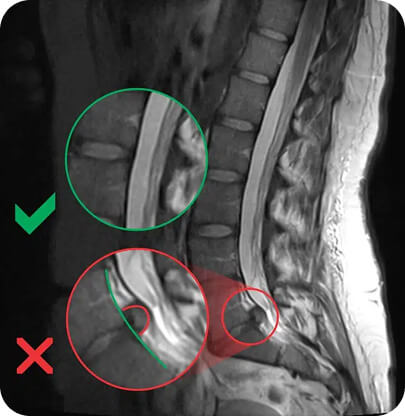

SLIKA MAGNETNE RESONANCE (MRI) - HERNIJA DISKA

Slika prikazuje razliko med primerno strukturo in pojavom hernija diska.